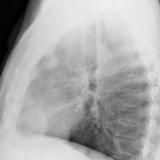

Case 9 Thymoma Lat

Date: 04/04/2010

Views: 3171